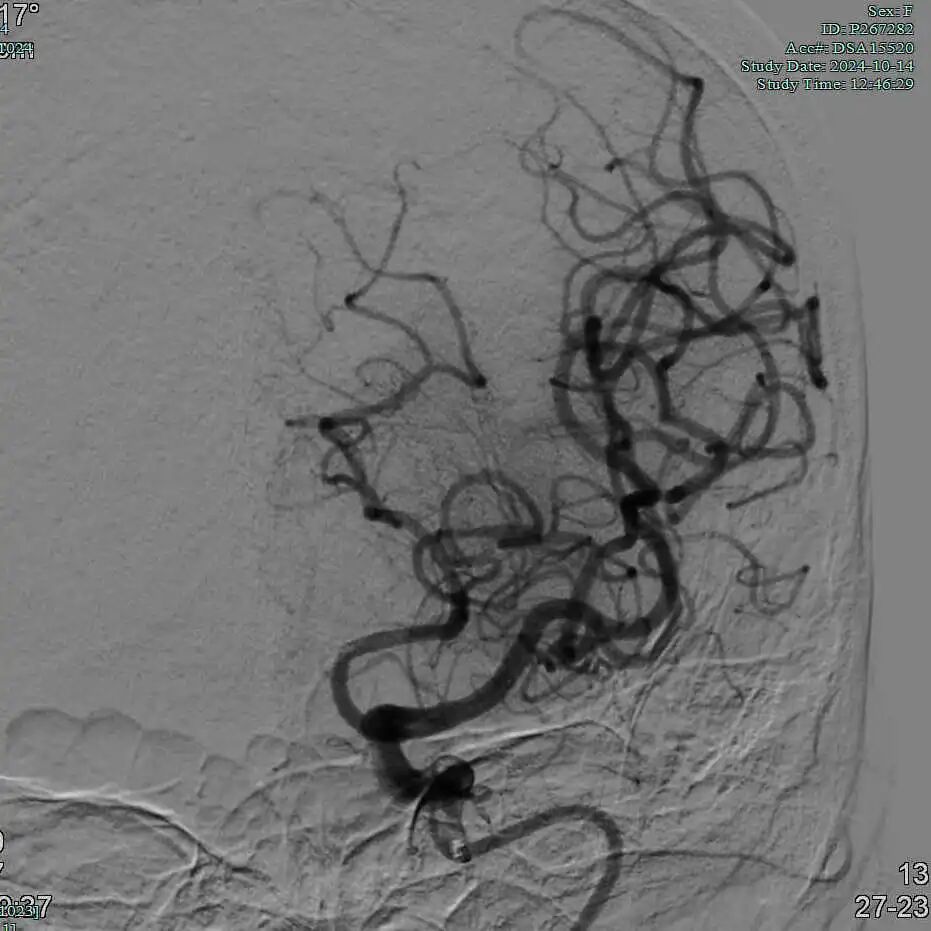

半回收取栓支架取栓后大脑中动脉上干血管再通。

动脉长鞘怎么置入有励可说|Locaste 088励楷长鞘及Tarvos微导丝在左侧大脑中动脉闭塞取栓术中的应用_https://www.jmylbn.com_新闻资讯_第18张

动脉长鞘怎么置入有励可说|Locaste 088励楷长鞘及Tarvos微导丝在左侧大脑中动脉闭塞取栓术中的应用_https://www.jmylbn.com_新闻资讯_第19张

动脉长鞘怎么置入有励可说|Locaste 088励楷长鞘及Tarvos微导丝在左侧大脑中动脉闭塞取栓术中的应用_https://www.jmylbn.com_新闻资讯_第20张

动脉长鞘怎么置入有励可说|Locaste 088励楷长鞘及Tarvos微导丝在左侧大脑中动脉闭塞取栓术中的应用_https://www.jmylbn.com_新闻资讯_第21张